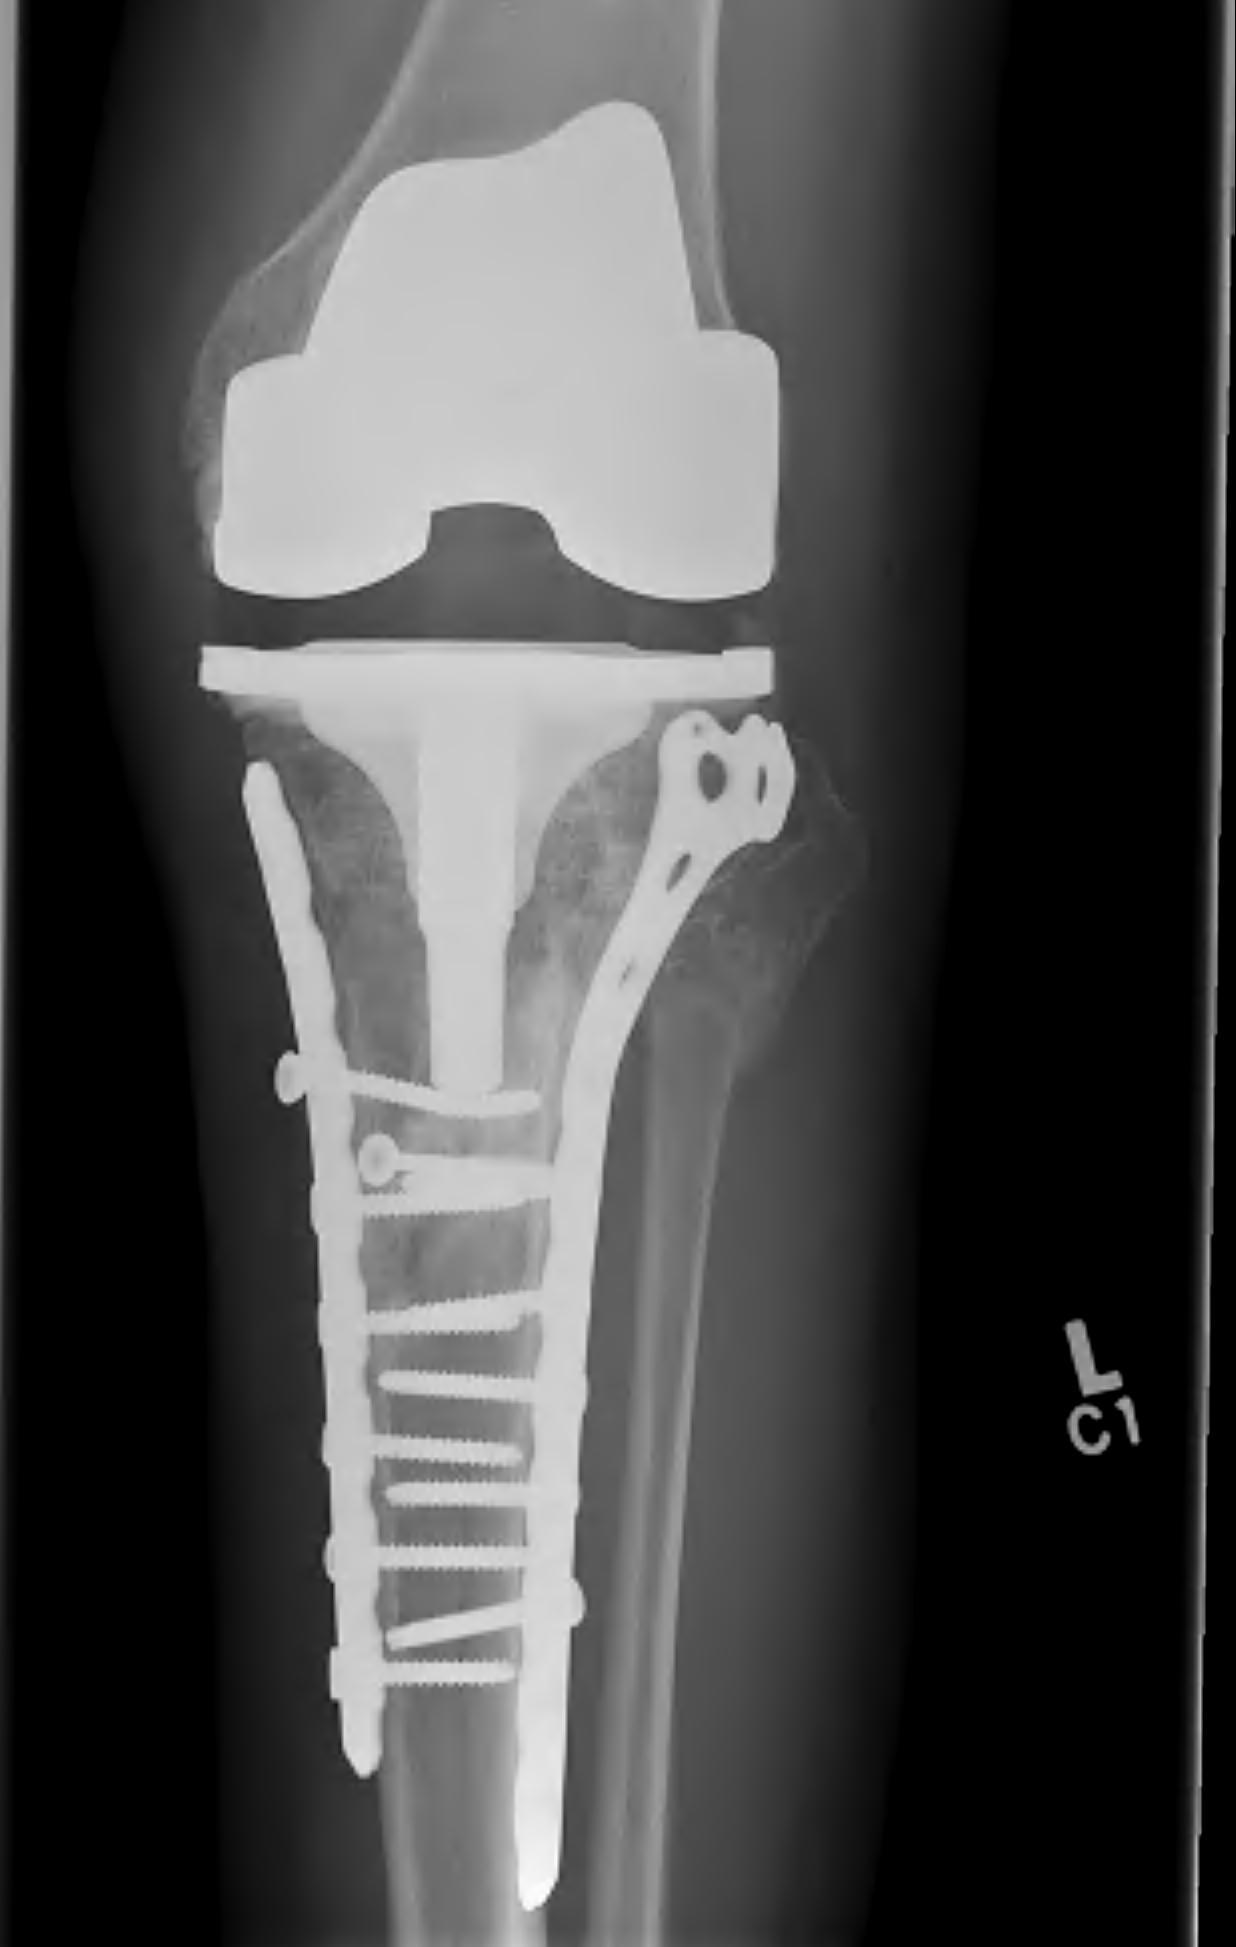

2. TKR

Scott et al. Bone Joint J 2015

- 31 patients with tibial plateau fracture requiring TKR at a mean of 24 months

- matched to a cohort of primary OA undergoing TKR

- increased rate of wound complications and stiffness in tibial plateau cohort

- otherwise, no significant difference in postoperative outcomes between the two groups